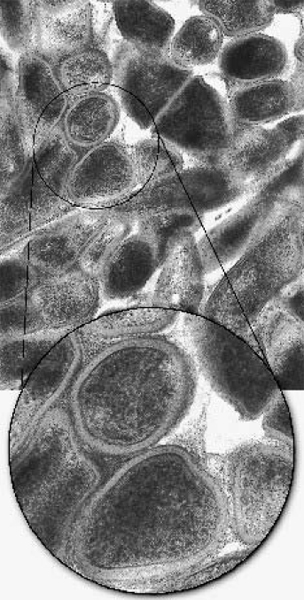

Fig. 1. – An electron microscope view of a whole cell preparation of Actinomyces israelii, strain L110B. Main picture shows a highly magnified view of the circular demarcated area of one of the three bacteria in the rectangular inset. The hairlike fimbriae can be seen protruding through a fuzzy coat which covers the entire surface of the cell. × 40 000; inset × 6760.

Electron microscopy of negatively stained whole-cell preparations showed that the body of the bacteria had a mottled appearance and the electron lucent inner aspect of the cell wall revealed irregular patches of electron-dense material. The cell surface was covered with a thick, fuzzy coat (Fig. 1). On some cells of strain L110B, hairlike structures could be seen protruding through the fuzzy outer coat. These hairy structures were evenly distributed over the entire surface of the bacterial cell wall (Fig. 1).